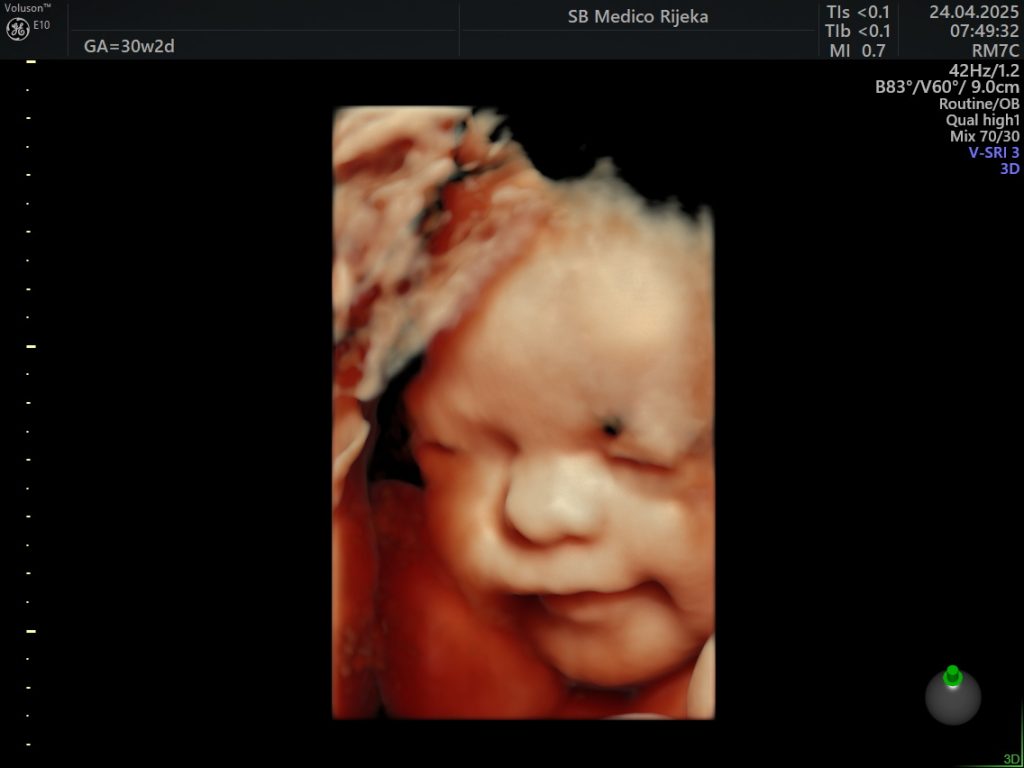

3D/4D ultrazvuk – trenutak koji ostaje zauvijek

Suvremeni 3D/4D ultrazvuk donosi novu dimenziju praćenja trudnoće. Omogućuje detaljniji prikaz razvoja djeteta prilikom svakog pregleda, a budućim roditeljima pruža priliku da na ekranu jasno vide lice svog djeteta, njegove pokrete i geste.

Iako je riječ o dijagnostičkoj metodi koja pomaže liječnicima u procjeni razvoja fetusa, taj pregled često ima i snažnu emocionalnu vrijednost, jer je to trenutak u kojem roditelji prvi put “upoznaju” svoju bebu.

U Medicu se 3D/4D ultrazvuk obavlja na najsuvremenijim uređajima visoke rezolucije koji omogućuju iznimnu jasnoću slike, a stručni tim ginekologa osigurava preciznu analizu i ugodno iskustvo pregleda.

Osim što doprinosi sigurnosti trudnoće, taj pregled mnogim roditeljima ostaje jedna od najljepših uspomena, jer je često to prvi osmijeh, zijevanje ili pokret njihove bebe koji imaju prilike vidjeti.